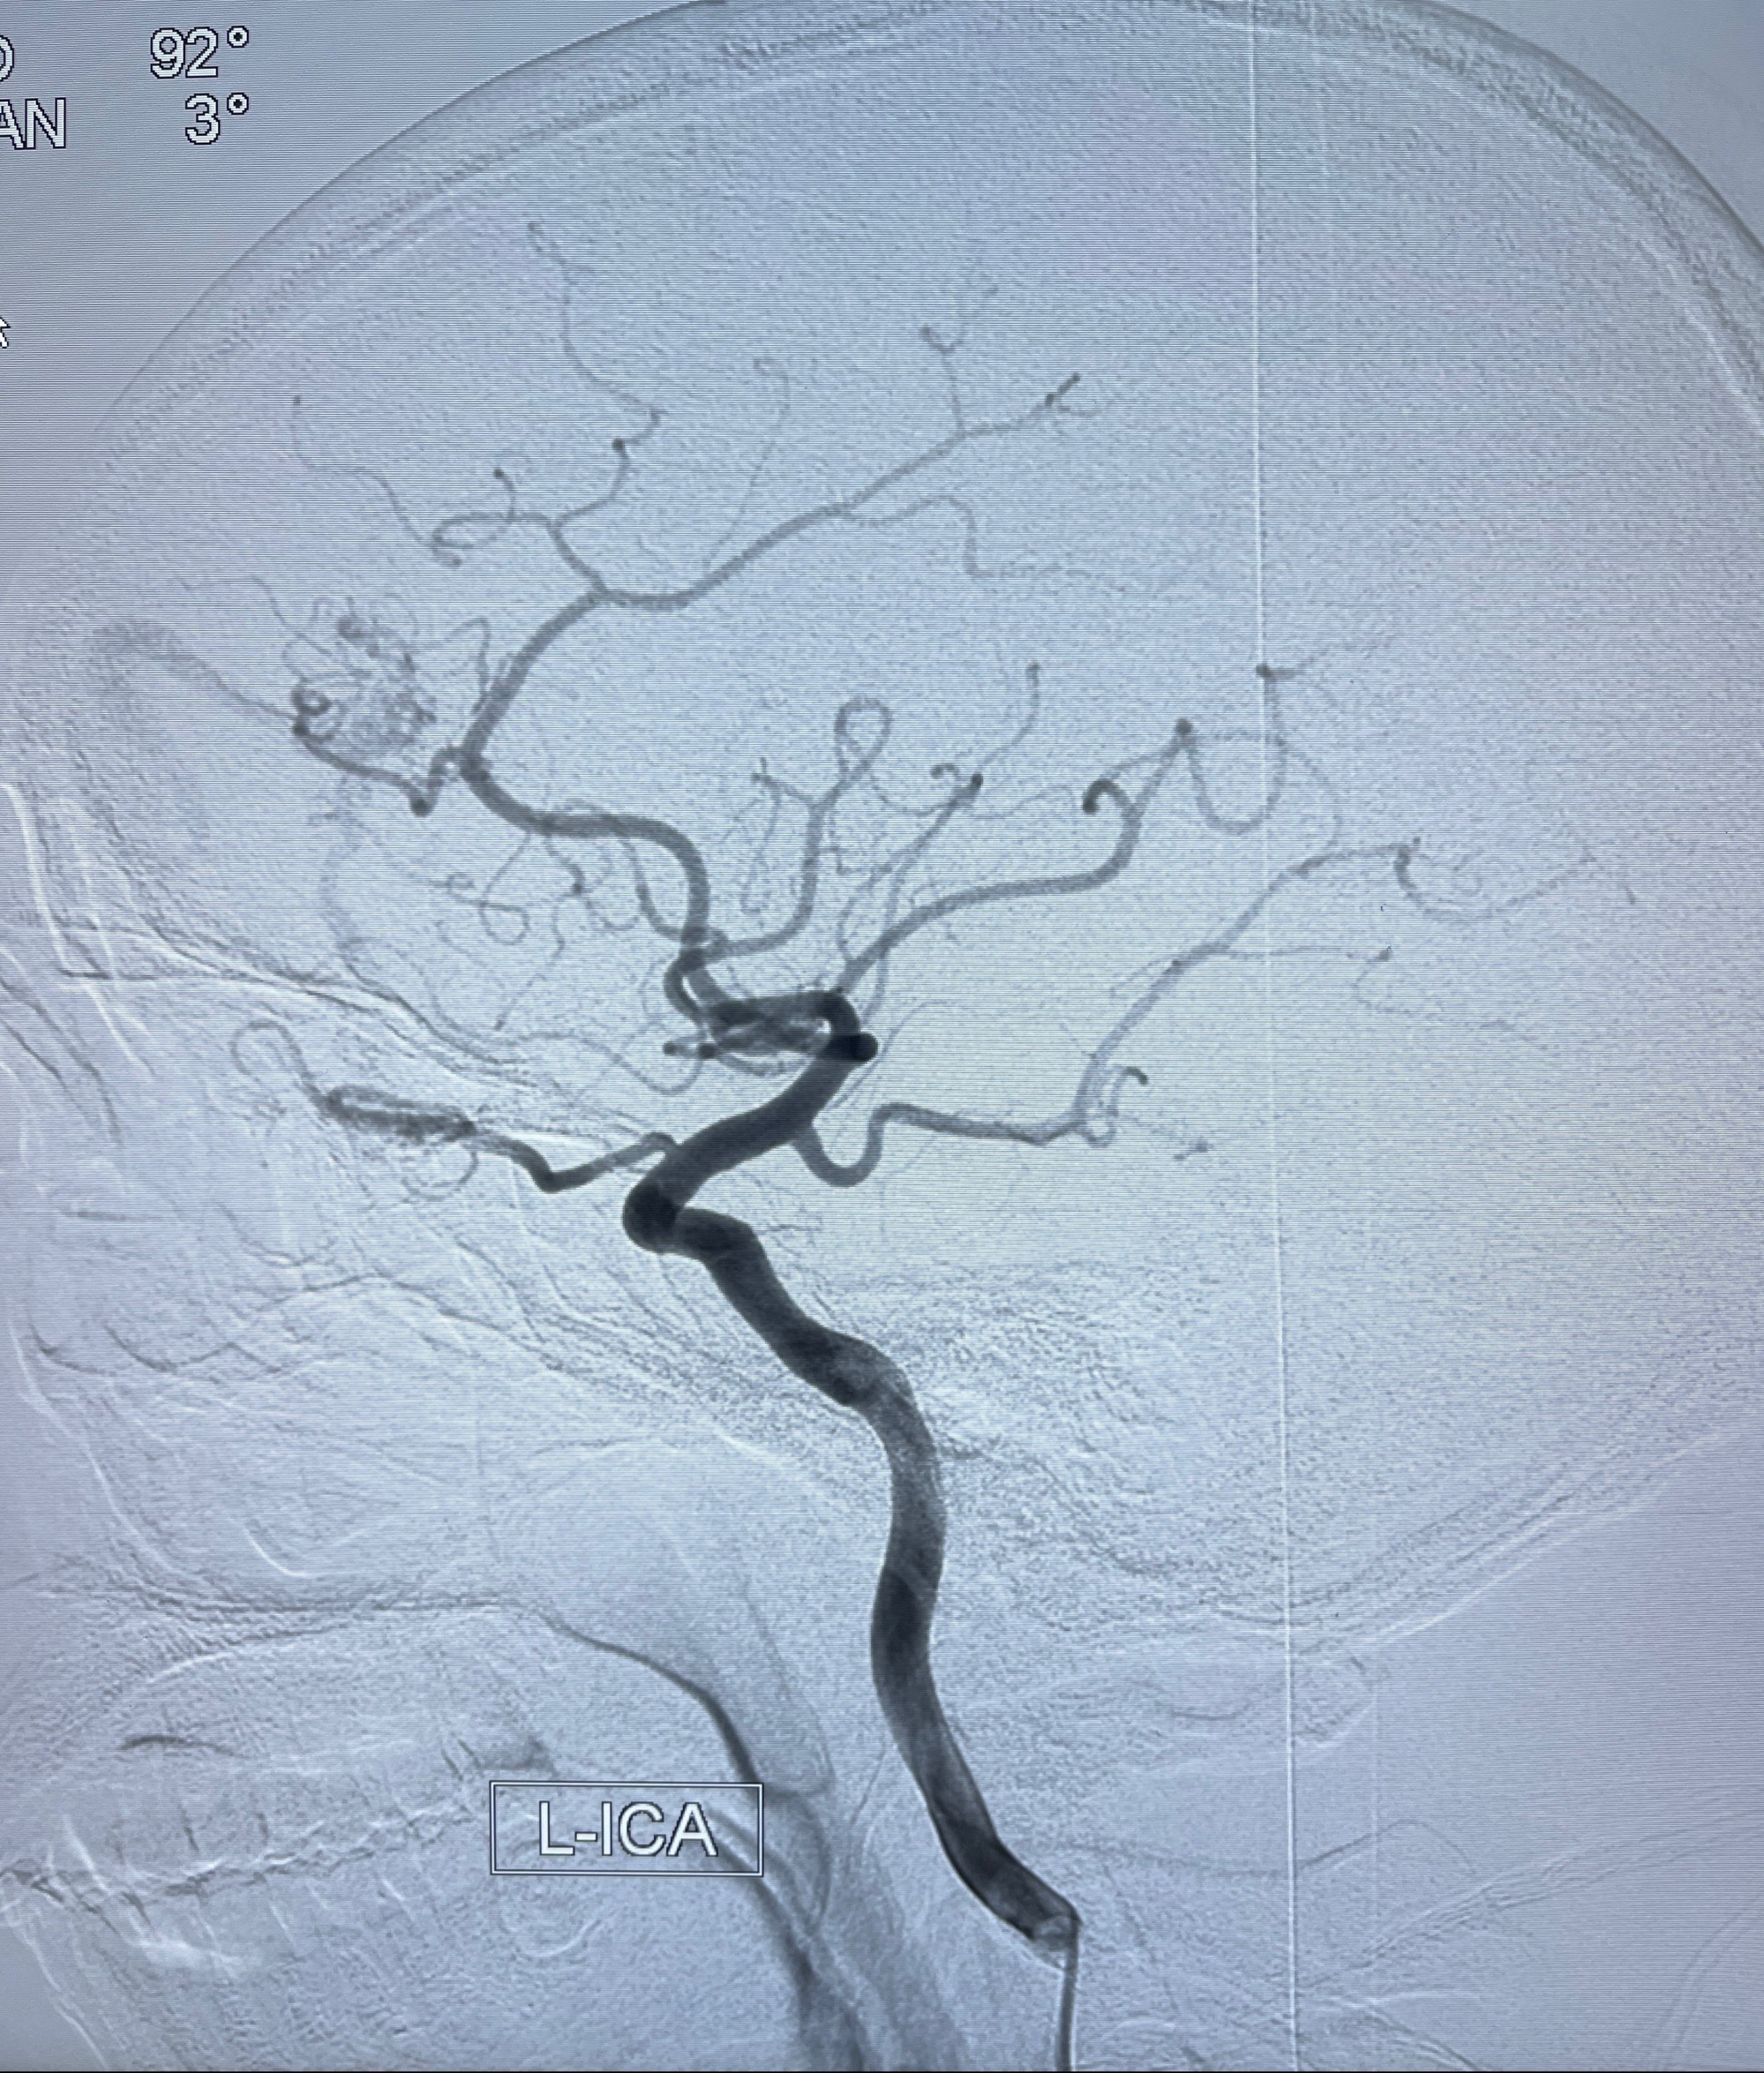

2023年8月21日]景德镇市第一人民医院脑血管造影检查,提示:主动脉弓、双侧颈总动脉、锁骨下动脉造影未见异常,左侧大脑前动脉静脉瘘。

2023-09-13全脑血管造影:前颅底硬脑膜动静脉瘘,供血动脉为双侧胼周动脉、眼动脉脑膜支,静脉向上矢状窦方向引流